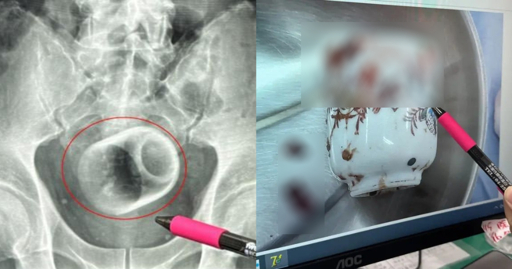

A doctor at the hospital pointed out that while inserting foreign objects into the bottom was not unheard of, they can cause immense damage to internal organs and be fatal.

These objects include baseballs, vibrators and coconuts, and could be inserted for stimulation or out of curiosity.